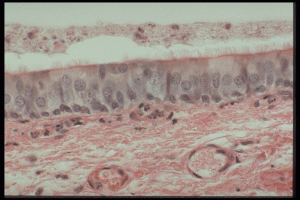

Epitheelweefsel komt voor in vele vormen in vele organen van het lichaam. Epitheelcellen kunnen zich